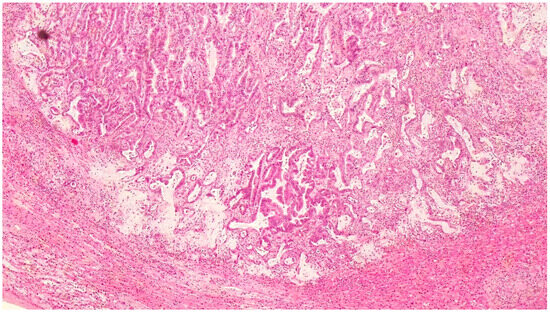

| Feature | Case 1 | Case 2 |

| Patient Demographics | 60-year-old Caucasian male | 28-year-old Caucasian female |

| Clinical Presentation | Incidental discovery of an 8 × 8 × 9 cm hepatic cyst | Presented with dyspnea, vomiting, jaundice, fever |

| Initial Diagnosis | Suspected hydatid cyst | Simple cyst, later adenocarcinoma with metastases |

| Diagnostic Methods | MRI, MRCP, ERCP, histopathological examination | CT, MRI, laparoscopic liver biopsy, histopathological examination |

| Tumor Characteristics | Large cystic mass, thin walls, internal septa, papillary projections, enhancing solid components | Large lesion in left hepatic lobe, hyperintensity in T2-weighted images, restricted diffusion, contrast enhancement |

| Treatment | Cyst resection, cholecystectomy | Thrombectomy, chemotherapy, supportive care |

| Surgical Findings | Partially exophytic floating soft mass | Extensive intrahepatic metastases, vascular involvement |

| Histopathological Findings | IPNB with foci of adenocarcinoma, oncocytic appearance, varying degrees of dysplasia, mucus within cyst | Adenocarcinoma with papillary clear cell and mucinous appearance, gland ectasis, cystic or pseudocystic aspects |

| Follow-up and Outcome | Initial recurrence-free survival for 8 years, recurrence treated with left hepatectomy, patient alive at 33 months post-second surgery | Disease progression despite aggressive management, patient died from hepatic failure |